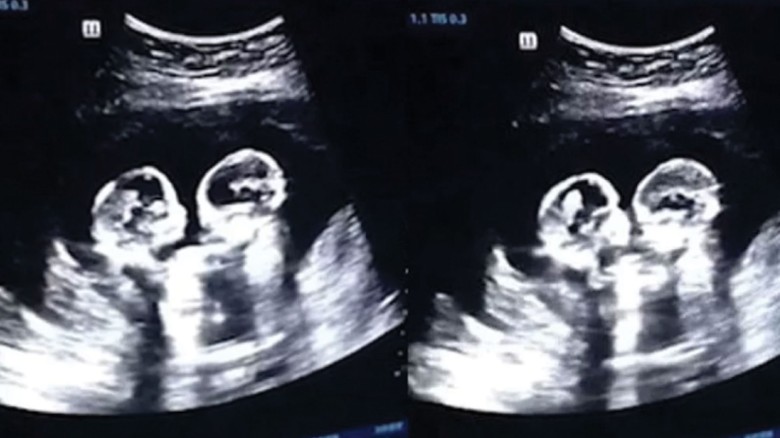

আলট্রাসনোগ্রামে মায়ের গর্ভে যমজ কন্যাশিশুর মারামারি!

চীনের ইয়ানচুন এলাকায় এক দম্পতি আলট্রাসনোগ্রাম করাতে গিয়ে এক অবিশ্বাস্য ঘটনার সাক্ষী হয়েছেন। আলট্রাসনোগ্রামের পর্দায় দেখা যায়, ওই নারীর গর্ভে থাকা যমজ দুই কন্যাশিশু যেন পেটের ভেতরেই মারামারি শুরু করেছে!

আলট্রাসনোগ্রামের মনিটরে দেখা যায়, অনাগত দুই সন্তান একে অপরকে লাথি মারছে এবং হাত তুলছে— দৃশ্যটি দেখে মনে হচ্ছে যেন তাদের মধ্যে সত্যিকারের 'ঝগড়া' চলছে। এমন বিরল দৃশ্য দেখে চিকিৎসকরাও হতবাক হয়ে যান।

চিকিৎসকদের মতে, গর্ভাবস্থায় যমজ সন্তানদের নড়াচড়া করা স্বাভাবিক ঘটনা হলেও, এমন ধরনের 'মারামারি সদৃশ' দৃশ্য খুবই বিরল।